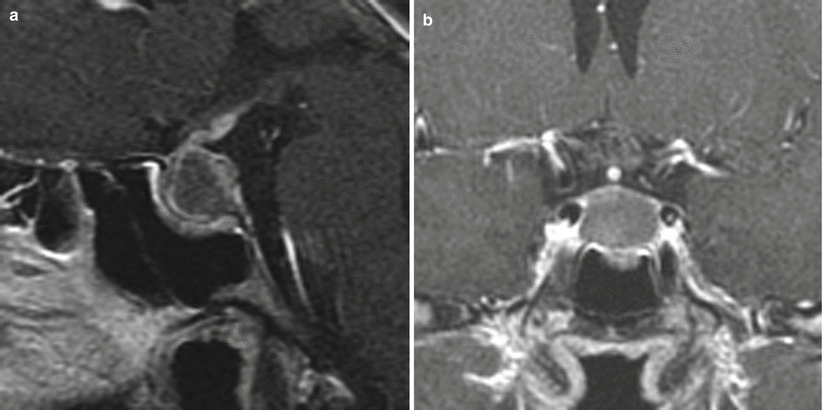

Classical features of Rathke cleft cyst on imaging. Top row showing